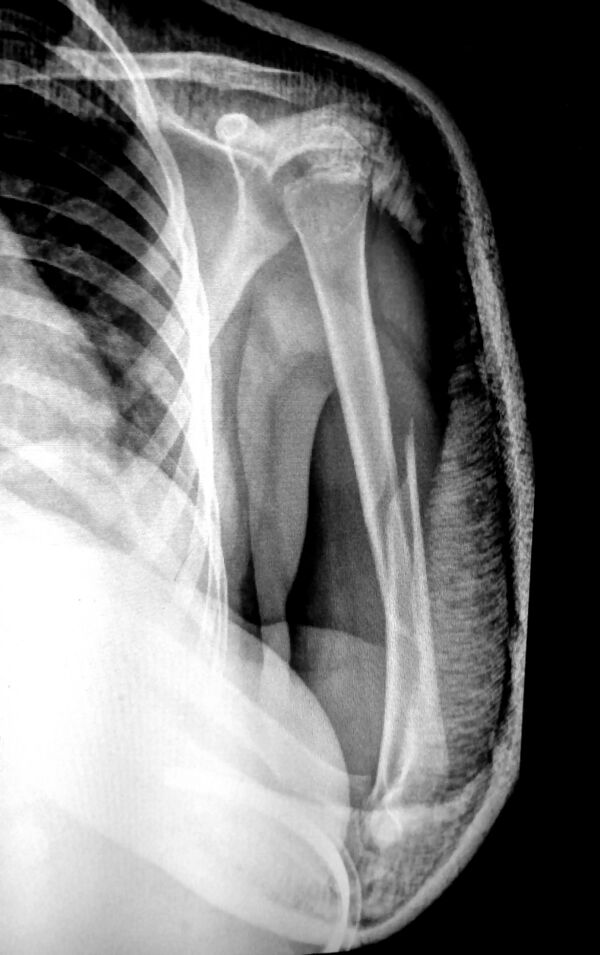

Рентгенограмма при многооскольчатом переломе плечевой кости в нижних отделах. Возможны внесуставные и внутрисуставные переломы плеча в нижних отделах. К внесуставным переломам нижних отделов плеча относятся надмыщелковые переломы, к внутрисуставным переломам — переломы блока, головчатого возвышения плечевой кости и межмыщелковые переломы.

С учётом механизма травмы Надмыщелковые переломы плеча подразделяются на разгибательные и сгибательные. Сгибательные надмыщелковые переломы встречаются чаще, возникают при падении на согнутую руку. Причиной разгибательного перелома становится падение на переразогнутую руку.

- Симптомы

Область плеча над локтевым суставом отечна, резко болезненна. Сгибательные переломы сопровождаются визуальным удлинением предплечья, при разгибательных переломах предплечье выглядит укороченным. Надмыщелковые переломы плеча могут сочетаться с вывихом костей предплечья. Диагноз устанавливается после рентгенографии.

- Лечение

При неосложнённых переломах область повреждения фиксируют гипсовой лонгетой на 3—4 недели. При большом смещении отломков и невозможности репозиции выполняют операцию.